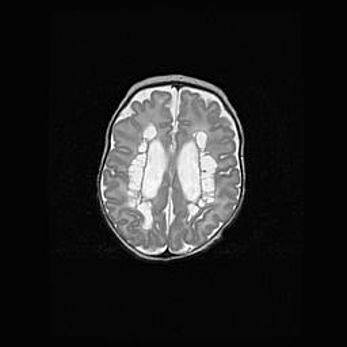

Лейкомаляция с кистозно-глиозной дегенерацией головного мозга.

Возраст: 2 месяца 25 дней

Вес: 6400 г

Окружность головы: 40 см

Срок гестации: 41 неделя

Лейкомаляцию относят к ишемически-гипоксическим повреждениям головного мозга, диагностируемым у новорожденных. При лейкомаляции в головном мозге обнаруживают очаги некроза, возникшие после тяжелой гипоксии и нарушения кровотока. В процессе морфогенеза очаги проходят три стадии: 1) развития некроза, 2) резорбции и 3) формирования глиозного рубца или кисты. Перивентрикулярная лейкомаляция (ПЛ) встречается примерно в 12% случаев среди новорожденных, обычно – у недоношенных детей, причем, частота ее зависит от массы, с которой младенец появился на свет. Наибольшее число малышей страдает лейкомаляцией, если масса при рождении 1500-2500 г.